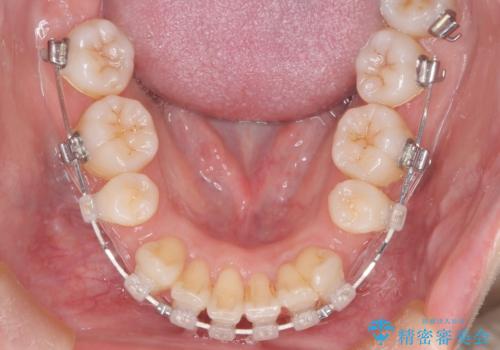

【審美装置】癒合歯がある方の治療

- 前歯の前突を主訴に来院されました。

下の前歯は癒合歯がある珍しいケースです。

治療に関しては小臼歯を4本抜歯して前歯を下げるような計画を立てて治療しました。

抜歯スペースの移動量を調整するために、矯正用アンカースクリューや親知らずを活用して治療を行いました。